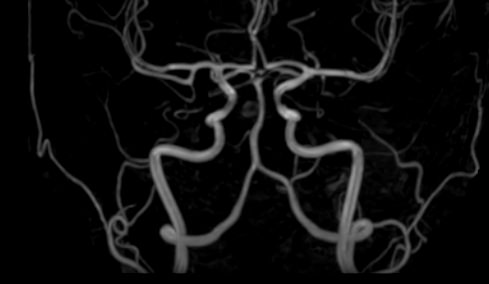

Стандартная МРТ головного мозга дает важную информацию о состоянии и структуре мозговой ткани для выявления большого числа заболеваний, в том числе опухолевых образований, демиелинизирующих заболеваний, воспалительных процессов головного мозга и мозговых оболочек. Стандартную МРТ головного мозга дополняет МР-ангиография, которая отображает состояние системы кровоснабжения головы и шеи. Компьютерная программа обрабатывает данные, полученные при сканировании, и формирует объемные изображения как самого мозга, так и сосудистой системы в отдельности без прилегающих тканей. Обе методики применяются одновременно и взаимодополняют друг друга, давая полную диагностическую картину.

Исследование предоставляет информацию о состоянии тканей головного мозга и оболочек, проходимости кровеносных сосудов, наличии и размерах опухолей, тромбов, гематом и других патологий. Изучив изображения, нейрохирург или другой специалист получает информацию о локализации патологии, степени повреждения тканей мозга, может принять решение о проведении операции либо контролировать ход лечения.